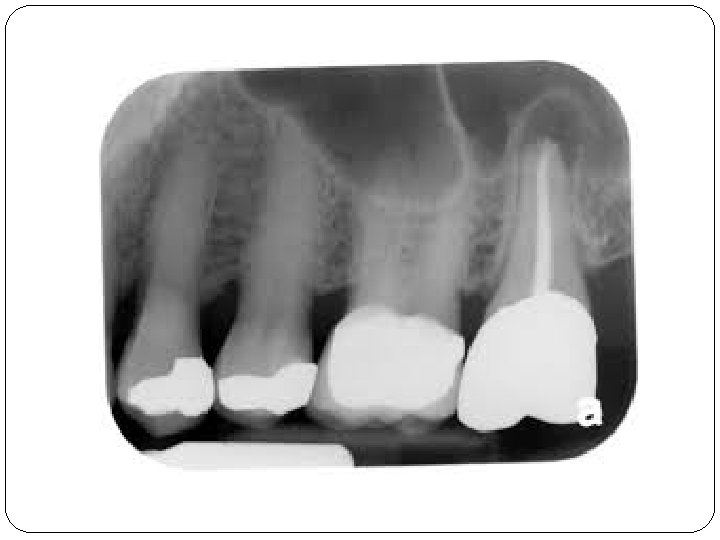

II. Chronische Apikale Parodontitis �Symptome: Langsamer Verlauf. Keine Schmerzen, Devitalität des betroffenen Zahnes. �Ursache: Infektion über den Wurzelkanal eines pulpentoten Zahnes �Röntgen: Im Röntgenbild apikale Aufhellung oder Parodontalspaltverbreiterung. +Knochensklero se/ Knochenverdünnung

II/B Parodontitis periapicalis chronica �Chronische Wurzelhautentzündung �Symptome: Es gibt sehr oft keine Symptome. �Röntgen: Periapikale Aufhellung-(Grenze ist nicht so scharf) Parodontalspaltverbreiterung �Histologie: Cyst > 1 cm (Fluidum) Granuloma < 1 cm (Granulationsgewebe)

Vor der Wurzelbehandlung Nach der Wurzelbehandlung